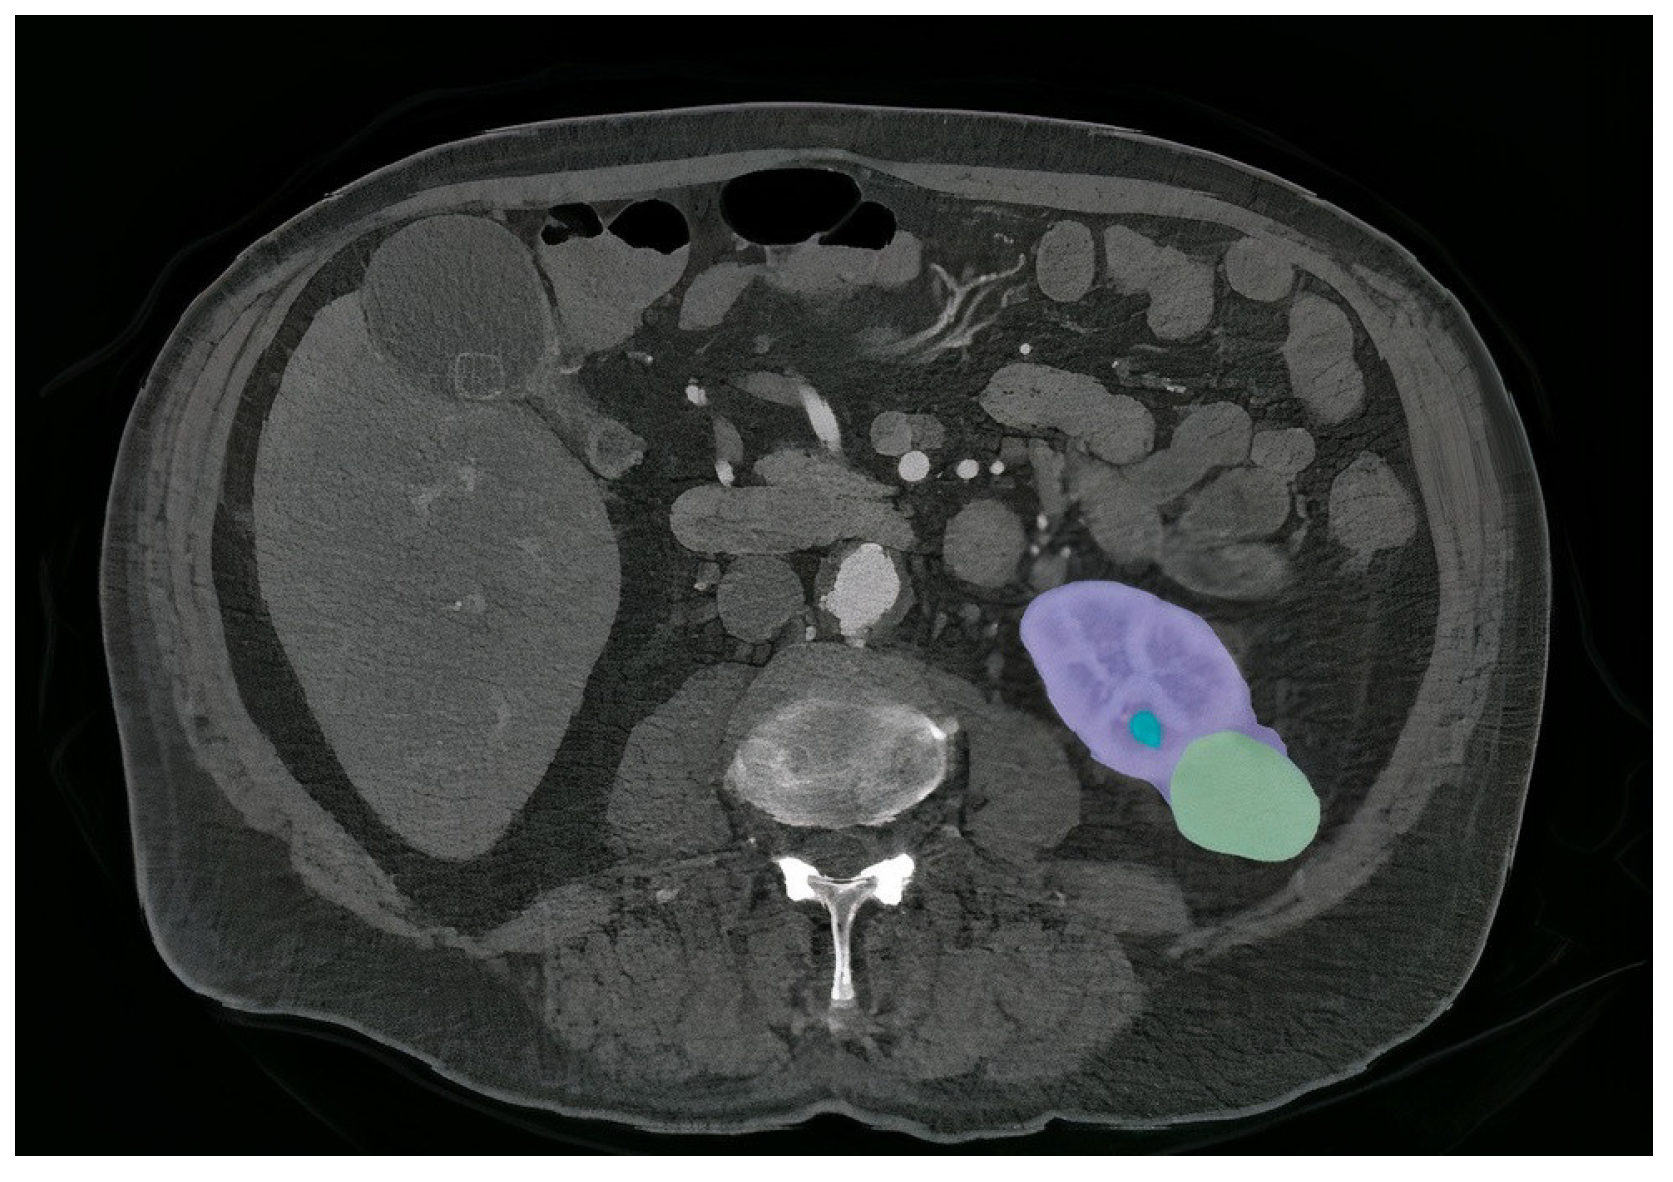

Figure 1. An example of a segmented slice from volume of CT scan Modality. The kidney region is shown in purple, the tumor is shown in green, and the cyst is shown in blue.

The kidneys serve a vital role in the human body by filtering waste products and toxins from the bloodstream [1,2]. Tumors, or cancers, result from the abnormal growth of cells and can manifest differently in individuals, leading to various symptoms. Early detection of kidney tumors (KT) is paramount for mitigating the risk of disease progression and preserving the patient’s life [2,3]. Although approximately one third of KT cases are identified after spreading to other areas, many remain asymptomatic and are incidentally discovered during unrelated medical evaluations. Kidney tumors can manifest as masses, cysts, or abdominal discomfort in patients, often unrelated to kidney function [4,5]. Nevertheless, some subtle symptoms or complications may arise due to KT, including low hemoglobin levels, weakness, vomiting, abdominal pain, hematuria (blood in urine), or elevated blood sugar levels. Anemia is also a common occurrence, affecting about 30% of KT patients [6,7]. Unfortunately, tumors and solid masses that develop within the kidneys frequently become cancerous. Detecting the presence of cancer is crucial in selecting the appropriate treatment method, as the prognosis and recovery rate often hinge on early identification. Computed tomography (CT) scans of the abdomen and pelvis are among the essential diagnostic tests used to ascertain the presence of kidney tumors. These scans provide specific characteristics that aid in tumor detection and assessment. Figure 1 illustrates a case of KT, depicting a renal mass lesion in the left kidney measuring approximately 4 cm (with the kidney in red and renal cancer in green). Given the life-threatening nature of tumors, accurate diagnosis is paramount, leading to various procedures aimed at assisting the physician [8,9]. Deep learning (DL) is a remarkably potent machine learning technology capable of autonomously acquiring numerous features and patterns without human intervention [10,11,12]. DL has empowered the development of predictive models for early tumor disease detection, with scientists relying on established pattern analysis techniques. DL algorithms have demonstrated superiority over traditional machine learning methods, yielding impressive results [13,14,15]. Furthermore, DL frequently achieves performance levels that match or exceed human capabilities, making it the preferred approach for handling image-related tasks [16,17]. This heightened recognition of DL in image processing, particularly within the medical domain, is attributed to the central role of radiology in extracting valuable insights from images.